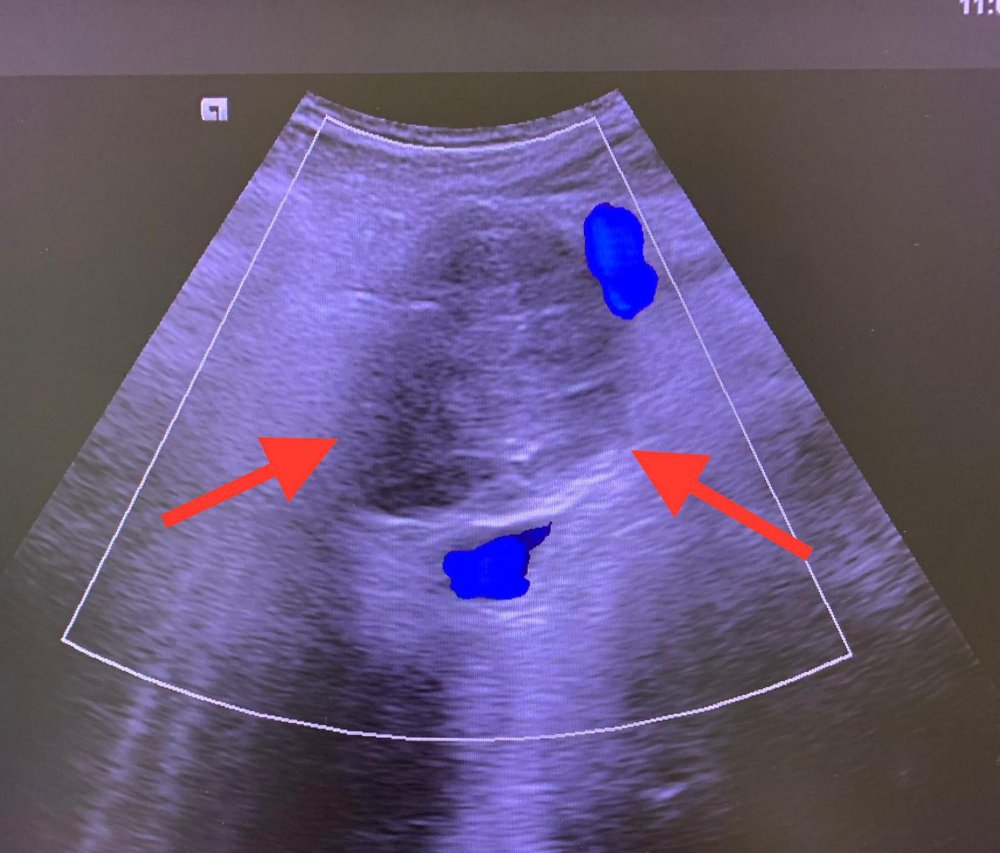

Ameliyat şansını yitiren hastalarda girişimsel işlemler, kemoterapi ve radyoterapi ile yaşam süresini uzatmanın söz konusu olabildiğini kaydeden Doç. Dr. Purbager sözlerini şöyle sürdürdü: "Pankreasın anatomik konumu nedeniyle ana damarlarla çok yakın ilişkisi mevcuttur. Ayrıca karın boşluğunun arkasında yer aldığından komşuluğundaki organlardan bu organa ve tümöre ulaşmak zordur. Girişimsel işlemler büyük bir tecrübe gerektirmektedir. Hastamıza 2009 yılında pankreas kanseri tanısı koyulmuş, başka bir merkezde ameliyata alınmıştır. Ancak ameliyat esnasında kitlenin damarlara yapıştığı anlaşılarak biyopsi alındıktan sonra kitle çıkarılmadan ameliyat sonlandırılmıştır. Hastamız 2010 yılında bize başvurduğunda kitlenin 5 santimetre çapında, çevre organlara ve damarlara yapışık olduğu görüldü. Bunun üzerine açık cerrahi yapmadan kapalı olarak renkli ultrasonla damarlar korunarak kitleye mikrodalga ablasyon (yakma) tedavisi uygulandı."

Komplikasyonsuz olarak tamamlanan işlemden 1 gün sonra hastanın taburcu edildiğini belirten Doç. Dr. Purbager, "Aralıklı olarak hasta kontrolleri yapıldı. 2 yıl sonra kitlede hafif boyutsal artış izlenince tekrar kapalı yöntemle etanol ablasyon tedavisi uygulandı. 2022 yılına kadar stabil olarak seyreden kitlede 1 santimetre boyut artışı saptanınca 3. kez etanol ablasyon uygulandı. Bu yöntemlerde amaç tümörün büyümesinin durdurulması, engellenmesidir. Bu 12 yıl süre zarfında hasta aktif olarak yaşamını sürdürüyor, mesleği olan çiftçiliği, arıcılığı yapıyor. Burada vurgulanması gereken bir nokta pankreas kanseri tanısı alan hastalarda cerrahi şansı varsa ilk tedavi yönteminin cerrahi olduğunun bilinmesidir. Ablasyon tedavisi sadece cerrahi şansı olmayan hastalara uygulanmaktadır ki hastamız Celal Açıkgöz de böyle bir hastaydı. Radyolojik girişimsel yöntem uyguladığımız hastamız 13 yıldır pankreas kanseriyle normal hayatını yaşıyor. Şu an tümör stabil, 6 santimetre takip edilecek, gerekirse tekrar ablasyon uygulanabilir" açıklamalarında bulundu.